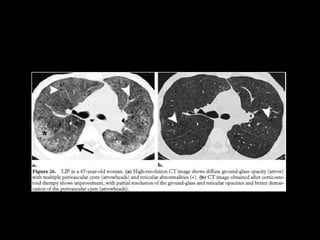

DIP • “alveolar macrophagepneumonia” • Vidrio esmerilado • LI y subpleural • Quistes aéreos, panalziación poco frecuente • DD: RB. NSIP: ausencia de fibrosis, bq x tracción • LBA: macrófagos

DIP

• Quistes aéreos, panalziación poco frecuente

• DD: RB. NSIP: ausencia de fibrosis, bq x